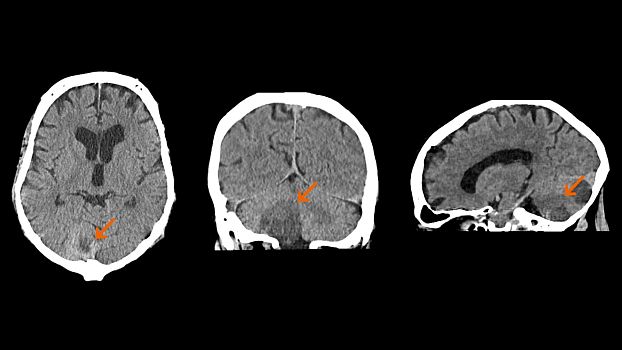

SOMATOM go.Up оптимизирует качество изображений и снижает лучевую нагрузку в рутинных неврологических исследованиях. SOMATOM go.Up отличается высокой скоростью сканирования и высоким качеством полученных изображений, что повышает качество диагностики особенно мелких сосудистых структур.